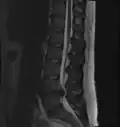

Lumbar disc herniation

Herniated lumbar disc

Lumbar disc herniations occur in the back, most often between the fourth and fifth lumbar vertebral bodies or between the fifth and the sacrum. Here, symptoms can be felt in the lower back, buttocks, thigh, anal/genital region (via the perineal nerve), and may radiate into the foot and/or toe. The sciatic nerve is the most commonly affected nerve, causing symptoms of sciatica. The femoral nerve can also be affected and cause the patient to experience a numb, tingling feeling throughout one or both legs and even feet or a burning feeling in the hips and legs.[22] A herniation in the lumbar region often compresses the nerve root exiting at the level below the disc. Thus, a herniation of the L4–5 disc compresses the L5 nerve root, only if the herniation is posterolateral.